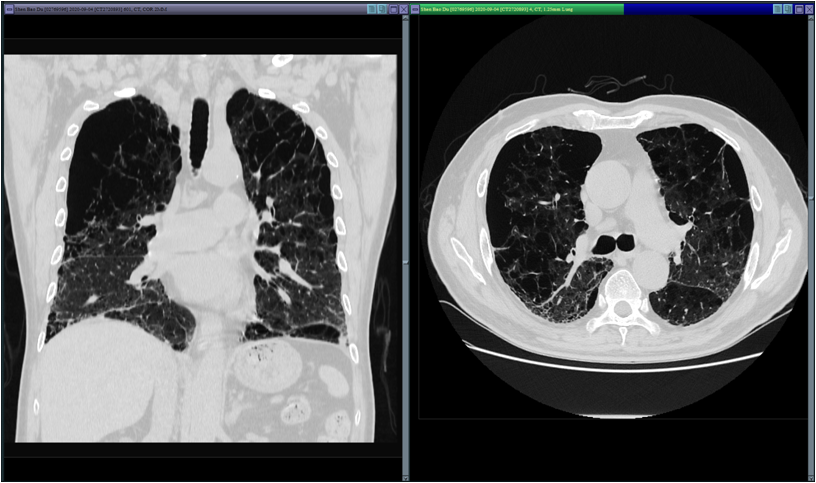

本文图片

季爷爷的肺部影像